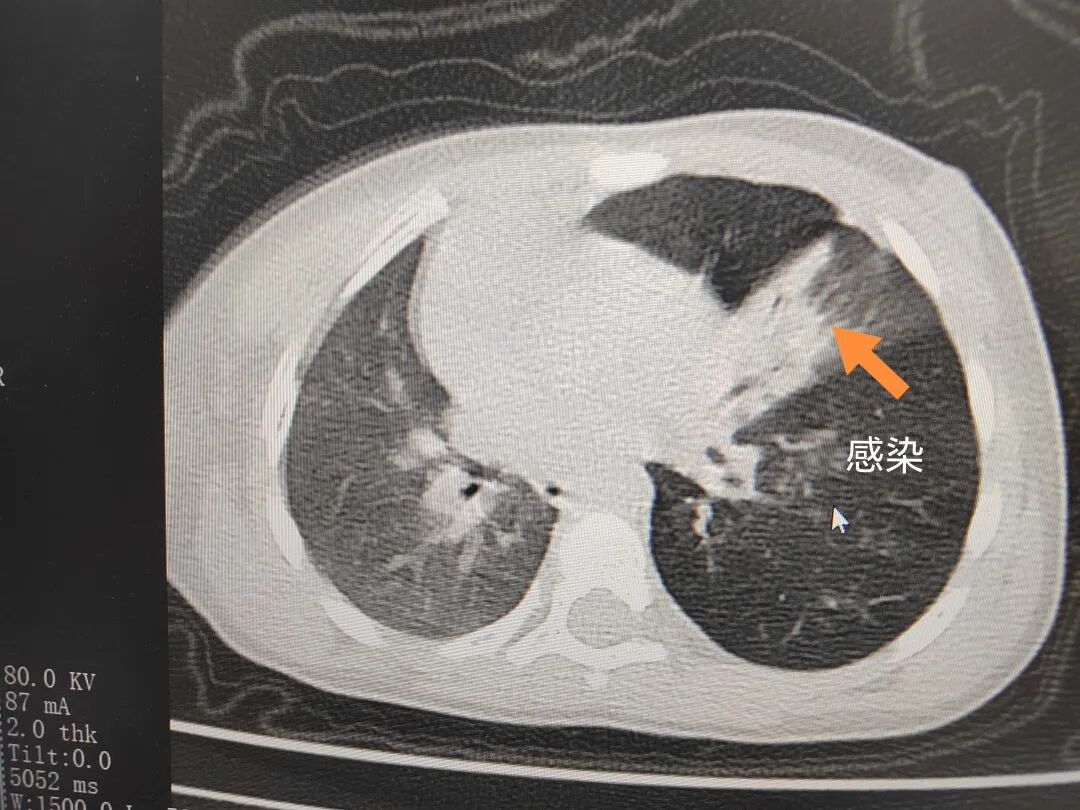

三天后(11月13日),趙寶出現(xiàn)高熱、咳喘加重,家長著急了,再次帶他來到醫(yī)院。CT檢查顯示左肺過度充氣,左肺上下葉支氣管主干見不規(guī)則高密度影,左肺上葉可見大片狀密度增高影,縱隔窗實(shí)變,提示為“左側(cè)支氣管內(nèi)異物并繼發(fā)性改變,左肺上葉舌段肺膨脹不全”。

市二院小兒呼吸內(nèi)科團(tuán)隊(duì)迅速為患兒制定了周密的手術(shù)方案,并很快安排了氣管鏡探查。術(shù)中,主治醫(yī)師田慧等憑借嫻熟的氣管鏡操作技術(shù)成功將異物大塊板栗取出。由于板栗在氣管內(nèi)存留時(shí)間較長,質(zhì)地軟糯易碎,大大增加了手術(shù)難度。檢查還發(fā)現(xiàn),異物停留部位的氣管黏膜已出現(xiàn)充血紅腫、糜爛,導(dǎo)致患兒住院時(shí)間相應(yīng)延長。此次事件給趙寶的家庭帶來了不小的驚嚇與擔(dān)憂,也再次為廣大家長敲響了警鐘。